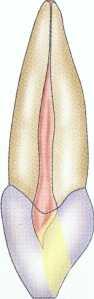

Maxillary Premolars

Although not all maxillary premolars have two canals,' they should all be approached from the assumption that they have separate buccal and lingual canals (Figure 2-20). This dictates a broad buccolingual access form that is somewhat constrained in the mesiodistal dimension (Figure 2-21). The maxillary premolar access is never round.

2-20 Access for maxillary premolars. A, Buccal view. B, Mesial view. C, Occlusal view.